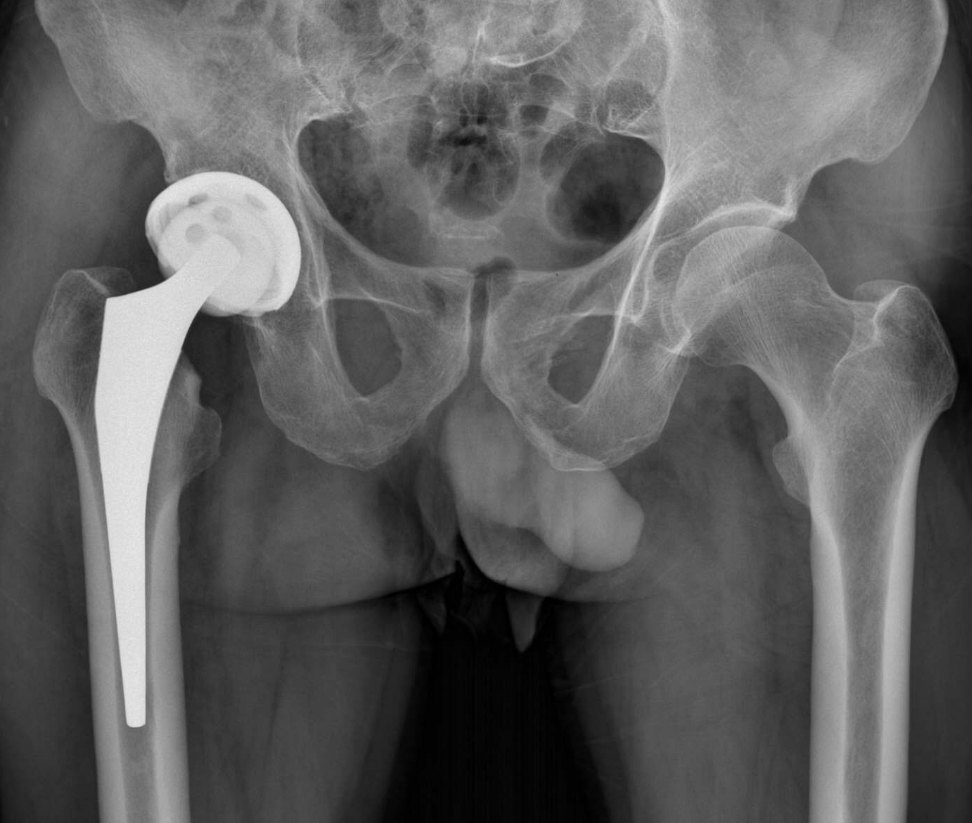

2、手術(shù)治療:對(duì)于嚴(yán)重骨頭壞死,可能需要進(jìn)行手術(shù)治療,如骨移植、關(guān)節(jié)置換等,手術(shù)治療的效果因個(gè)體情況而異,需在專業(yè)醫(yī)生的指導(dǎo)下進(jìn)行。